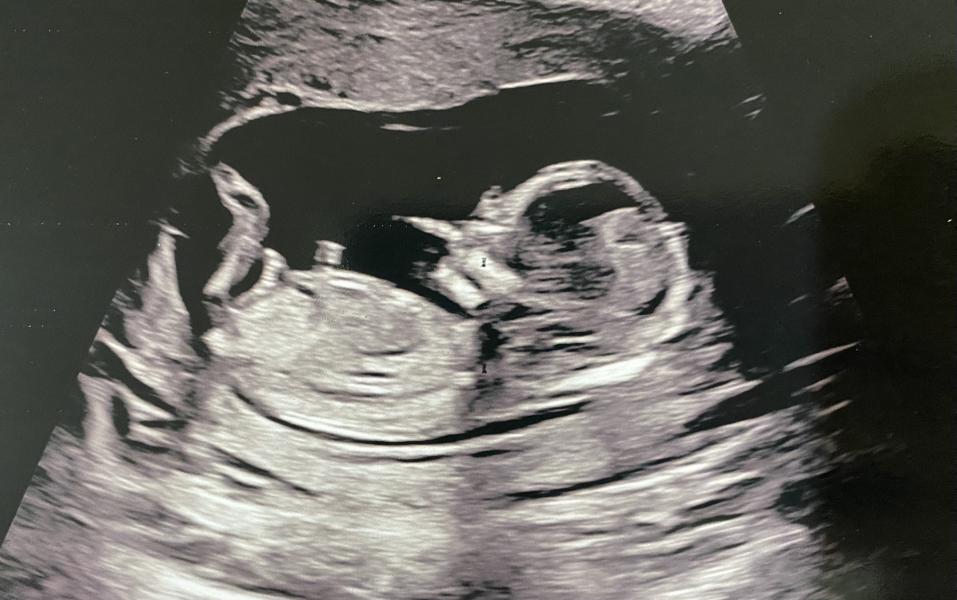

Сегодня был первый скрининг

Как думаете кто?)

На фото кажется что малыш мальчик 🥰

я по-моему научилась определять пол🥲скажите потом кто